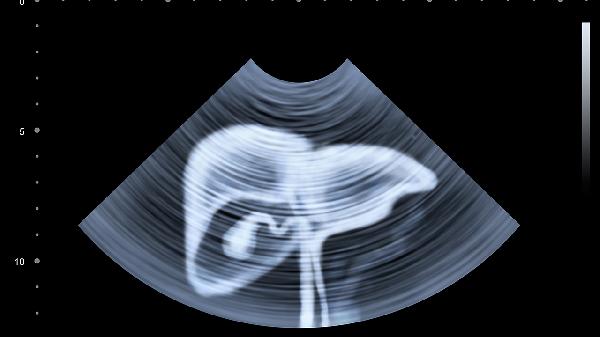

丙肝患者需建立规律作息,保证23点前入睡,避免熬夜加重肝脏负担。建议每周进行3-5次中等强度有氧运动,如八段锦、快走等,每次30-45分钟。严格戒酒并避免使用肝毒性药物,每3-6个月复查肝功能、肝脏超声及丙肝病毒定量。合并肝硬化者需定期进行胃镜检查,预防食管胃底静脉曲张破裂出血。保持乐观心态,可通过正念冥想缓解焦虑情绪,必要时寻求专业心理支持。